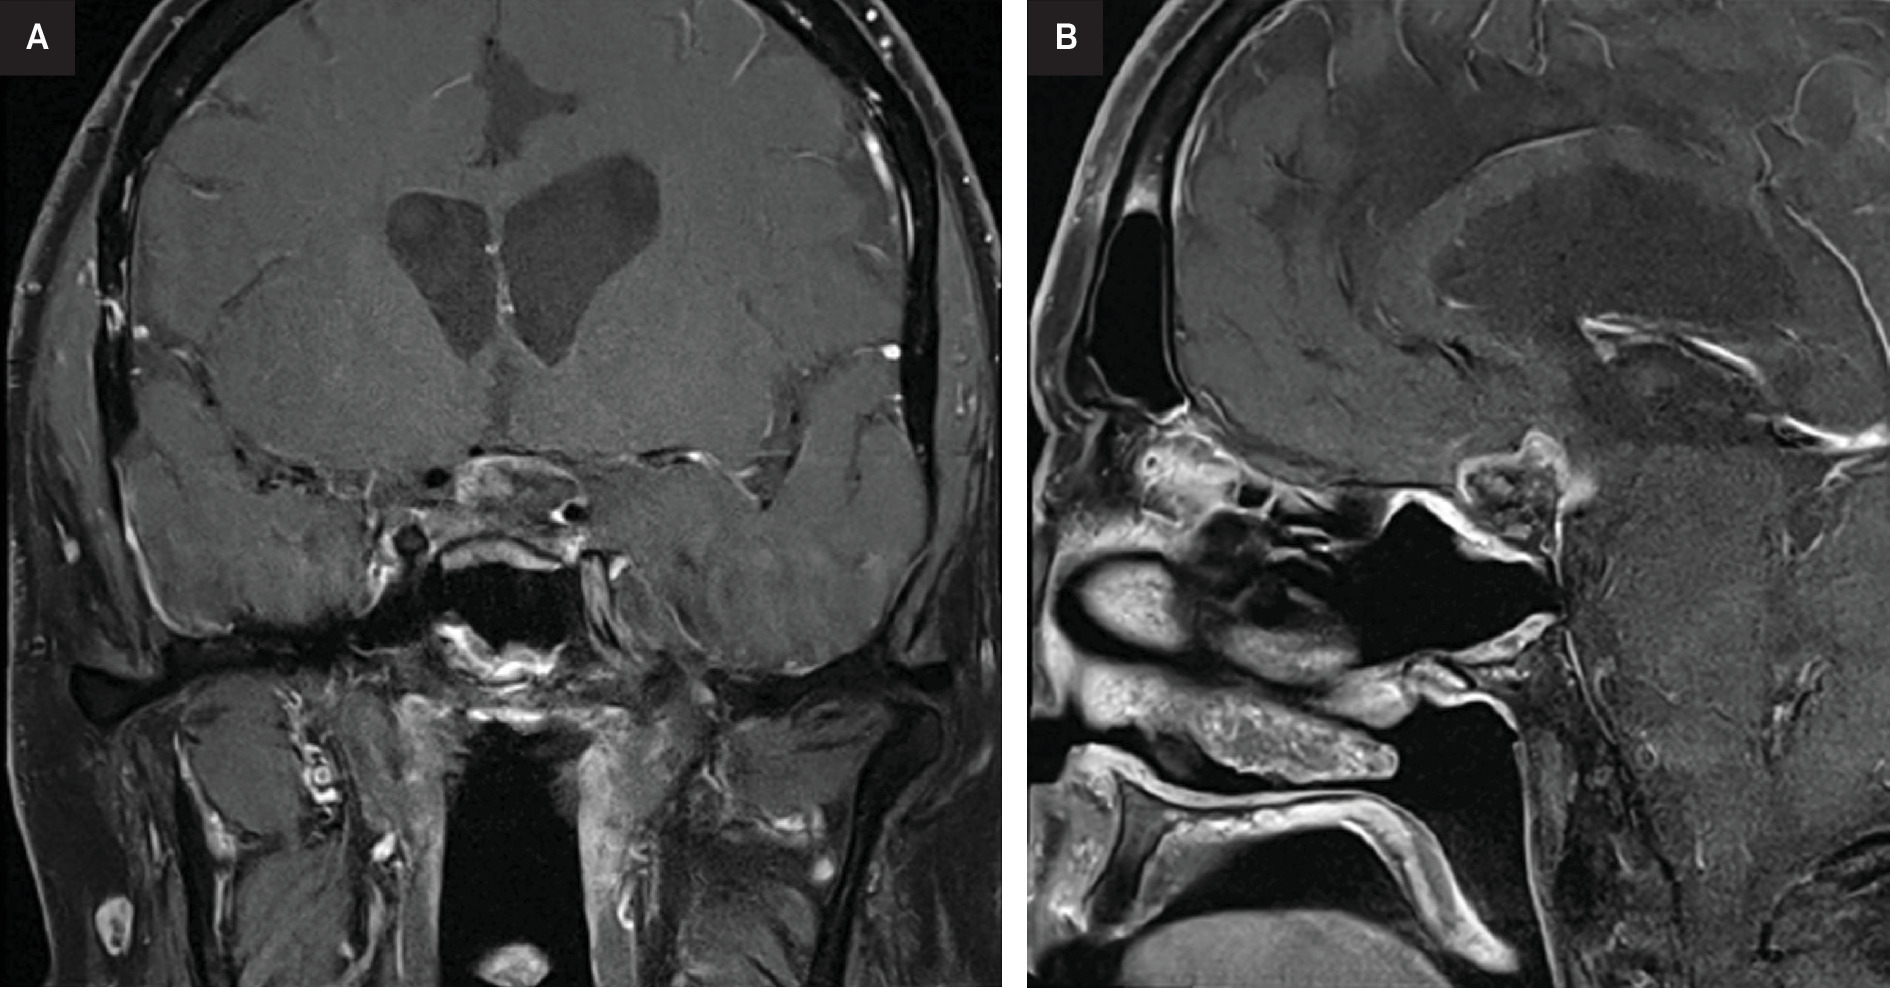

At this time, after a multidisciplinary discussion, the patient was referred to radiation oncology for consideration of additional RT. Ultimately, he was treated to a dose of 28 Gy in 14 fractions using 6 MV photons with 2 non-coplanar VMAT arcs (Figure 2). He again experienced no immediate side effects except for significant fatigue. MRI scans at 3 and 6 months post re-RT demonstrated a decrease in size and enhancement of the suprasellar abnormality with stable vision (Figure 3).